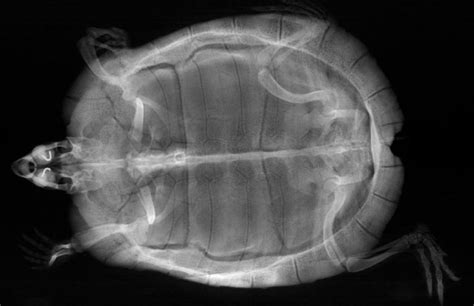

Alright, my fellow reptile aficionados, now for the really cool part: deciphering what your vet sees when they’re looking at that lateral turtle X-ray ! It’s like having a secret window into your turtle’s world, revealing all sorts of anatomical wonders and potential hidden issues. When your vet holds up that X-ray film (or points to the digital image on the screen), they’re not just seeing a jumble of shadows; they’re looking for specific structures and densities that tell a story about your turtle’s health. The lateral view provides a fantastic, uncluttered perspective that highlights the relationships between different organs and systems, making it incredibly powerful for diagnostic purposes. Let’s break down some of the key anatomical features they’re scrutinizing on a side view turtle X-ray .

Shell and Skeletal System

First up, let’s talk about the shell and the skeletal system . On a lateral turtle X-ray , the shell, comprising the carapace (top) and plastron (bottom), appears as a dense, bony outline. The vet will be looking closely at its integrity , checking for any signs of fractures, hairline cracks, or bone lesions that might not be visible externally. Sometimes, a trauma that seemed minor on the outside could have caused significant internal shell damage, and the side view X-ray is crucial for assessing this. They’ll also be evaluating the bone density of the shell and other skeletal structures, like the spine and limb bones. Reduced bone density, often appearing as thinner or less opaque bones on the X-ray, can be a tell-tale sign of Metabolic Bone Disease (MBD) , a common and serious condition in turtles caused by imbalances in calcium, phosphorus, and vitamin D3. MBD can manifest as generalized bone demineralization, pathological fractures, or abnormal bone growth. The lateral view allows for a clear assessment of the vertebral column, running along the length of the turtle’s body, checking for alignment, compression fractures, or any abnormal growths. The limb bones – humerus, radius, ulna, femur, tibia, fibula – are also visible, and the vet will be looking for fractures, dislocations, or other signs of injury or disease. Since turtles can be surprisingly resilient, they might not always show obvious signs of pain, making the X-ray an essential tool for uncovering these hidden skeletal problems. The clarity offered by the side view helps differentiate bone abnormalities from overlying soft tissues, ensuring an accurate diagnosis of skeletal health. The bony architecture of the shell, in particular, can reveal growth plate issues in younger turtles or degenerative changes in older ones, providing a comprehensive assessment of the animal’s osteological status.

Soft Tissue Structures and Organ Assessment

Now, moving deeper, the lateral turtle X-ray provides an incredible window into the soft tissue structures and internal organs . This is where the side view really shines, allowing for the assessment of organs that would be heavily superimposed in a top-down image. One of the most important areas is the lungs . In a lateral X-ray , the lungs appear as relatively clear, air-filled spaces located dorsally (towards the back) within the shell. The vet will be meticulously examining these lung fields for any abnormal densities, fluid accumulation (which would show up as hazy or opaque areas), or granulomas (small, dense masses). These findings are classic indicators of respiratory infections like pneumonia, which are common in turtles, especially those kept in improper environmental conditions. The side view helps distinguish lung pathology from other dense structures, such as the shell or overlying limbs, giving a much clearer picture of the severity and distribution of the infection. A healthy lung should appear clear and well-inflated, and any deviation from this normal appearance is a cause for concern.

Next, the digestive system. The gastrointestinal (GI) tract , including the stomach and intestines, can be visualized. On a lateral X-ray , the vet looks for signs of impaction – foreign bodies like substrate, rocks, or other indigestible items that can get stuck. These show up as dense, sometimes oddly shaped, objects within the gut lumen. They also assess for gas distension within the intestines, which can indicate poor gut motility or blockages. The bladder is another key structure. If your turtle has bladder stones (uroliths) , these will appear as dense, often round or oval, radio-opaque structures within the bladder, which is located ventrally (towards the belly) within the pelvic canal. The lateral view is excellent for confirming their presence and estimating their size and number. For female turtles, the reproductive organs are a crucial focus. If a female is gravid (carrying eggs), the side view X-ray will clearly show the eggs within the oviducts, allowing the vet to count them, assess their size, and check for any signs of egg binding (dystocia), where eggs are unable to be laid. This is vital information for managing potential reproductive complications. Other structures, like the liver and kidneys , can sometimes be indirectly assessed for changes in size or density, though specialized imaging might be needed for definitive diagnoses for these organs. The overall soft tissue architecture, including fat pads and muscle density, can also give clues about the turtle’s general body condition and nutritional status. The remarkable detail provided by the lateral turtle X-ray ensures that your vet has the most comprehensive visual information to make an accurate diagnosis and develop an effective treatment plan, making it an indispensable tool for maintaining your turtle’s health and well-being.